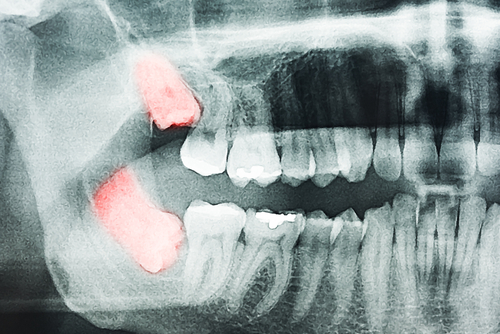

Recovering from Wisdom Tooth Surgery: Timeline

Having your wisdom teeth removed is almost a rite of passage for many adults and teenagers. It is one of the most common procedures we perform here at Dental Care of Beverly Hills. Naturally, the first question most patients ask us once they sit in the consultation chair is: “How long until I feel normal […]